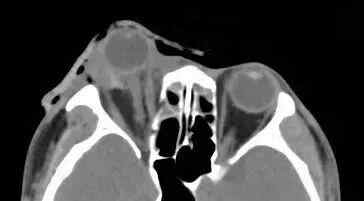

据厦门眼科中心眼外伤及眼底病二科副主任医师吴东海回忆,接诊时,陈先生的右眼眼球脱出眼眶,肿胀充血,眼睛无法正常闭合。他的视力几乎丧失,眼球上下方都有大面积的结膜裂伤。辅助检查的影像学结果显示,陈先生的伤眼近一半已脱出眼眶,眼球壁上还有星星点点的异物存留。

眼球脱出的医学影像示例

所幸陈先生视神经、眼外肌肉未发生断裂,眼球壁也未破裂,但他的状况依然危急。为防止角膜长时间暴露,医生立即对陈先生的伤眼做了包扎处理。待陈先生的身体状况稳定后,医生通过手术将陈先生的眼球还纳。